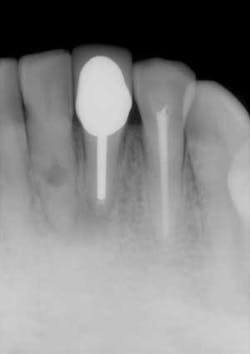

I offer the four clinical examples below to help you distinguish between internal and external resorption.- The outline of the canal in No. 24 is easily seen through the lesion, unaltered, and appearance is slightly ragged and irregular (figure 5).

- Diagnosis given to the patient at the time lesion was first noticed: internal resorption. As you can see, a root canal was completed, but no changes noted to the lesion. Patient continued to have discomfort post root canal therapy (figure 6).

- Reassessment: external resorption confirmed by a 3-D scan. Tooth was recommended for removal and an implant was placed.